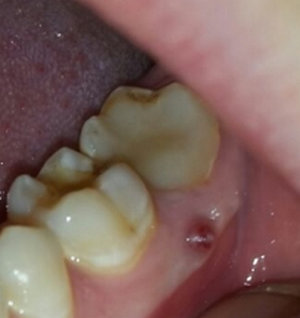

Подскажите, пожалуйста. Болела десна около недели, незначительно. Позже образовался какой-то шарик, похожий на прыщик. А после, во время еды что-то стало мешать и вот появилось непонятное новообразование из десны. На ощупь твердое, беспокоит во время приема пищи.

Подскажите, что это может быть?

Очень сложно определить, но все Ваши симптомы говорят и свищевом выходе. То есть, на верхушках зуба имеется воспалительный процесс.